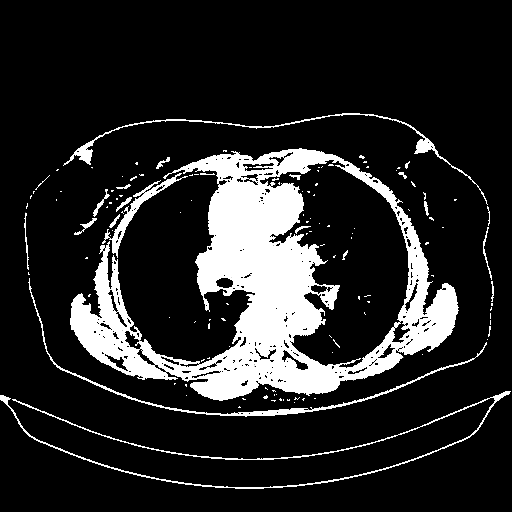

Generated VENOUS CT scan (A→B translation)

Full window (WL 1023.5, WW 4095 β†’ Low βˆ’1024, High +3071)

Actual HU range: [-1024.0, 3071.0]